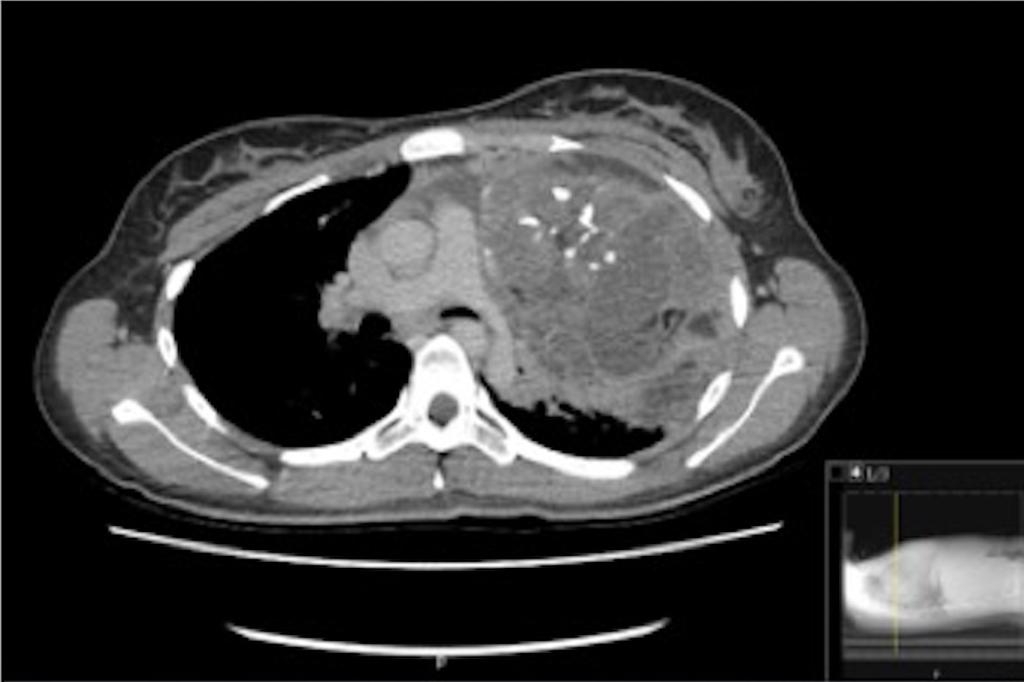

Gepubliceerd: Week 11 - 2020 204 deelnemers Een 19-jarige vrouw bezoekt de SEH vanwege een productieve hoest en een pijnlijke linker thoraxhelft. Bij auscultatie van de linker long is verscherpt ademgeruis te horen. Wat is er aan de hand? Wat is uw diagnose? Antwoord maligne lymfoom ectopisch schildklierweefsel thymoom matuur teratoom Antwoord controleren